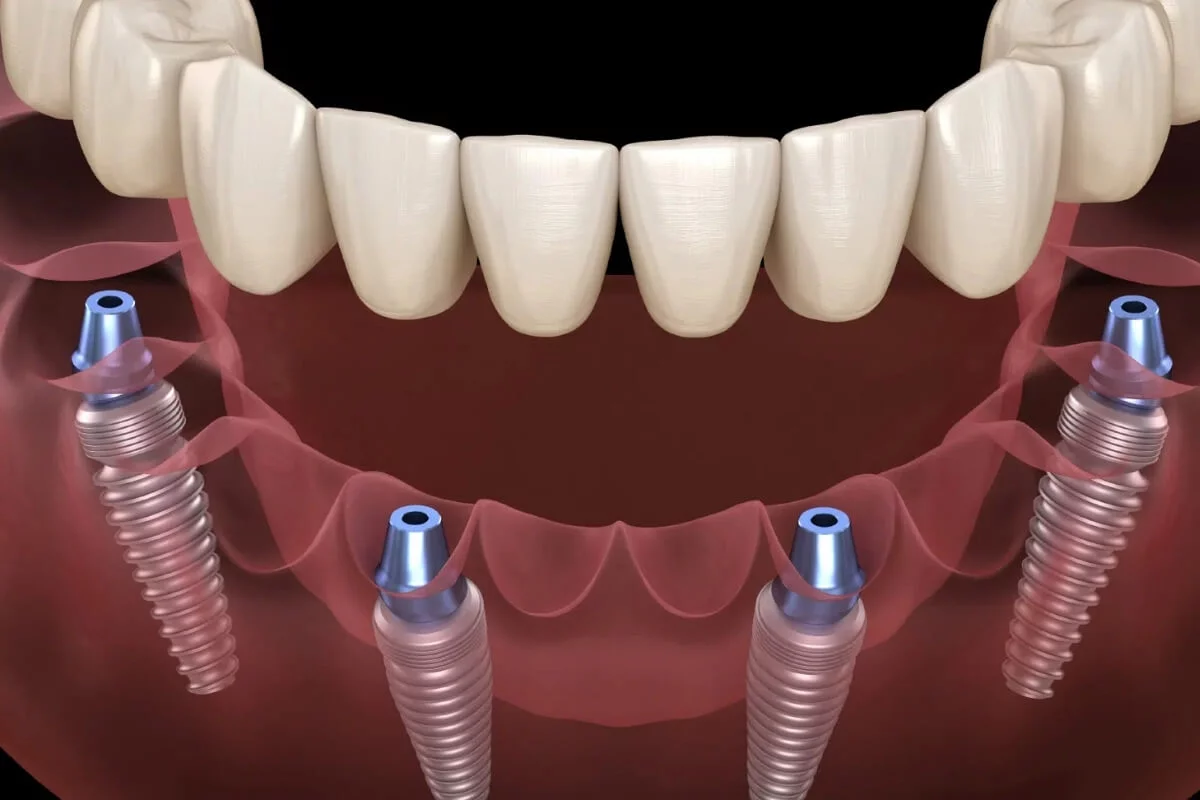

dis protezleri icin bakim ve onarim hizmeti

Ürün/Hizmet Açıklaması

dis protezleri icin bakim ve onarim hizmeti;